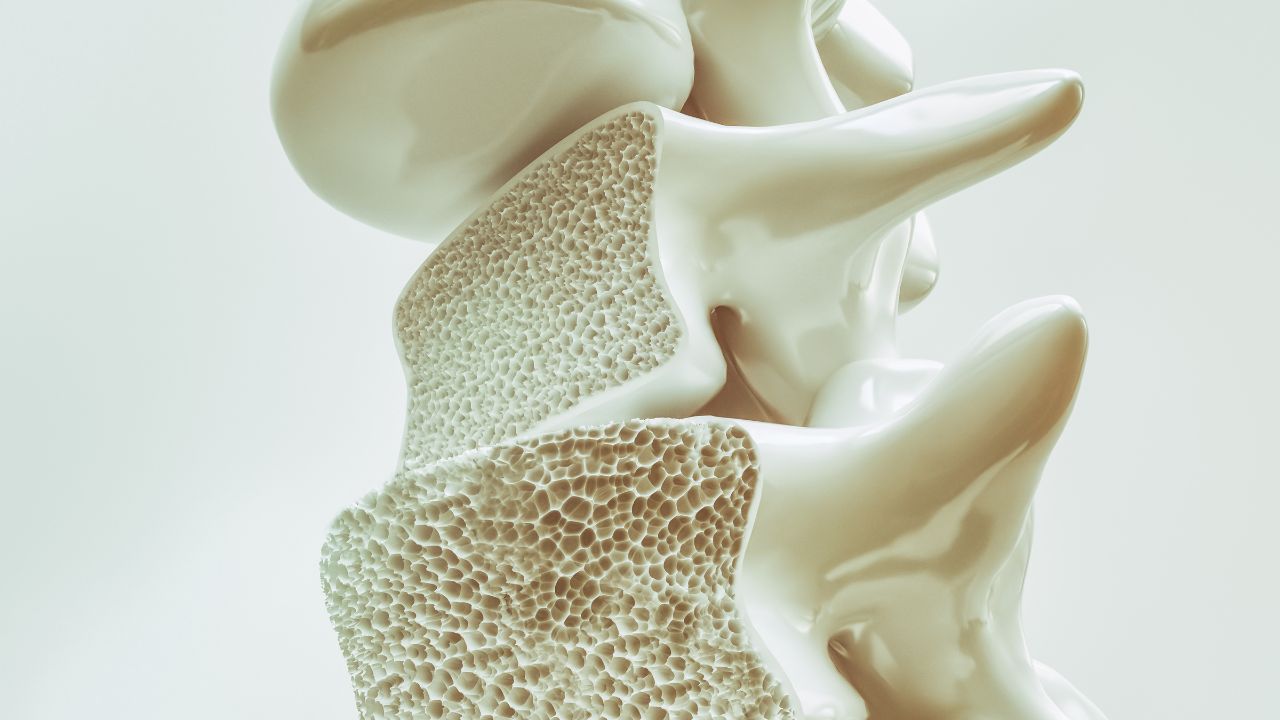

Os ossos são tecidos vivos que estão em constante processo de remodelação, com células especializadas (osteoblastos) construindo novo osso e outras (osteoclastos) removendo o osso antigo. O estrogênio atua como um regulador desse processo, inibindo a atividade dos osteoclastos e promovendo a formação óssea.

Com a diminuição dos níveis de estrogênio na menopausa, o equilíbrio entre a formação e a reabsorção óssea é alterado, com a reabsorção superando a formação. Isso resulta em uma perda líquida de massa óssea, tornando os ossos mais porosos e frágeis.

Estudos mostram que as mulheres podem perder até 20% da densidade óssea nos primeiros 5 a 7 anos após a menopausa. Essa perda acelerada é o principal fator que contribui para o desenvolvimento da osteoporose, uma doença silenciosa que torna os ossos tão frágeis que podem fraturar-se com facilidade, mesmo com traumas leves.

As fraturas mais comuns associadas à osteoporose ocorrem na coluna vertebral, quadril e punho, e podem levar a dor crônica, incapacidade e perda de qualidade de vida.